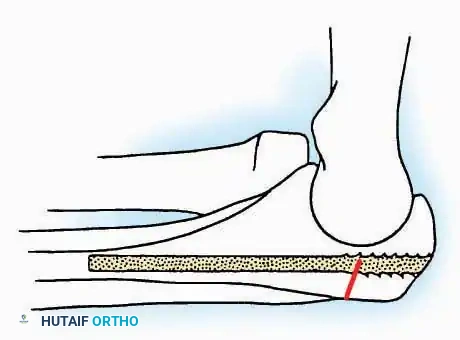

Lateral Approach (Extensile Lateral)

This is the workhorse approach for open reduction and internal fixation (ORIF) of displaced intra-articular calcaneal fractures.

Indications: ORIF of calcaneus fractures, lateral wall exostectomy, subtalar arthrodesis.

Positioning: Lateral decubitus with the operative leg up, or supine with a large bump under the ipsilateral hip to internally rotate the leg.

Surgical Technique:

* Incision: Begin the incision on the lateral margin of the Achilles tendon near its insertion. Extend it distally to a point 4 cm inferior and 2.5 cm anterior to the lateral malleolus. (For trauma, a classic L-shaped extensile incision is often used, dropping straight down anterior to the Achilles, then curving gently toward the base of the 5th metatarsal).

* Superficial Dissection: Divide the superficial and deep fasciae. It is imperative to create a "full-thickness" flap containing skin, subcutaneous fat, and periosteum to prevent flap necrosis.

* Nerve Protection: The sural nerve crosses the proximal and distal limbs of this approach. It must be identified and protected within the anterior flap.

* Deep Dissection: Isolate the peroneal tendons (longus and brevis). Incise and elevate the periosteum below the tendons to expose the lateral wall of the calcaneus.

* Tendon Management: If severe deformity or infection is present, the peroneal tendons may be divided via Z-plasty and repaired at the conclusion of the case, though this is rarely necessary in modern fracture care.